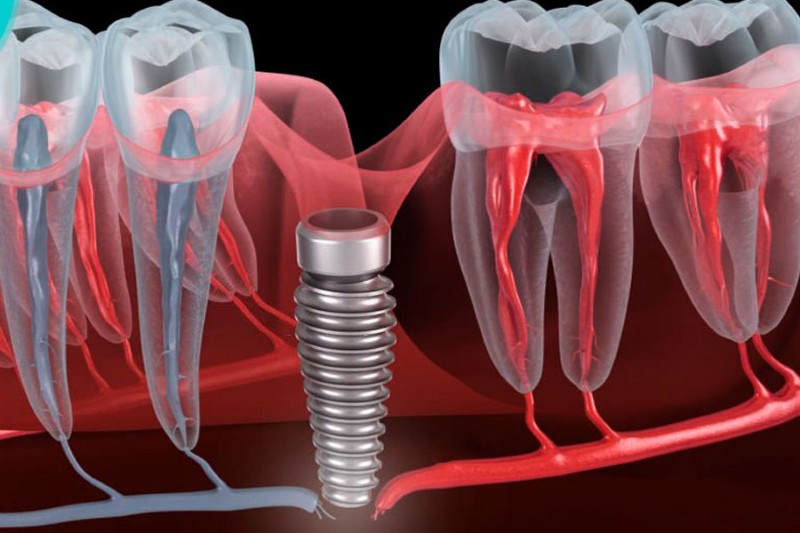

Trồng răng implant là quy trình phẫu thuật cấy ghép một trụ titanium vào xương hàm để thay thế cho chân răng đã mất, từ đó hỗ trợ đặt răng giả lên trên. Mặc dù phương pháp này có tỷ lệ thành công cao, không thể phủ nhận rằng cũng có những rủi ro nhất định liên quan đến kỹ thuật và sức khỏe của bệnh nhân.

Trụ Implant bị đào thải (Không tích hợp xương)

Một trong những yếu tố quan trọng quyết định sự thành công của cấy ghép implant là khả năng tích hợp giữa trụ titanium và xương hàm. Tuy nhiên, không phải lúc nào trụ implant cũng có thể tích hợp thành công. Nếu trụ không được tích hợp với xương, tình trạng đào thải sẽ xảy ra, dẫn tới việc implant không phát huy hiệu quả.